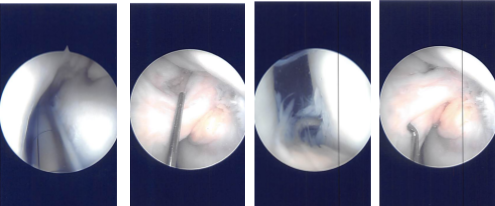

We pulled the patient on tourniquet 2.53. Laterally a working portal was made and using a 2.58 incision. Examination of the patellofemoral joint showed arthritis and posterior surface of the patella as well as on the trochlea. Examination of the medial Joint space showed medial femoral condyle arthritis, grade 2 to grade 3. Patellofemoral finding was also grade 3.

The scope was moved to 3.26 and found to be intact. Lateral compartment was examined and found to have a tear of the lateral meniscus, medial margin. The medial entry portal was made with direct access to the lateral condyle using a spinal needle. The lateral meniscus was trimmed using a shaver.

Intraoperative Arthroscopy Images

Chondroplasty of patellofemoral joint, medial femoral condyle was also performed using shaver. The knee was thoroughly irrigated. The closure was done by 4-0 and 3-0 nylon. Injection of 80 mg of Depo-Medrol and 19 mL of Xylocaine was performed. Dressing was done using 4 x 4, ABD, Webril, and ACE wrap. The patient extubated and moved to the recovery area in stable condition.